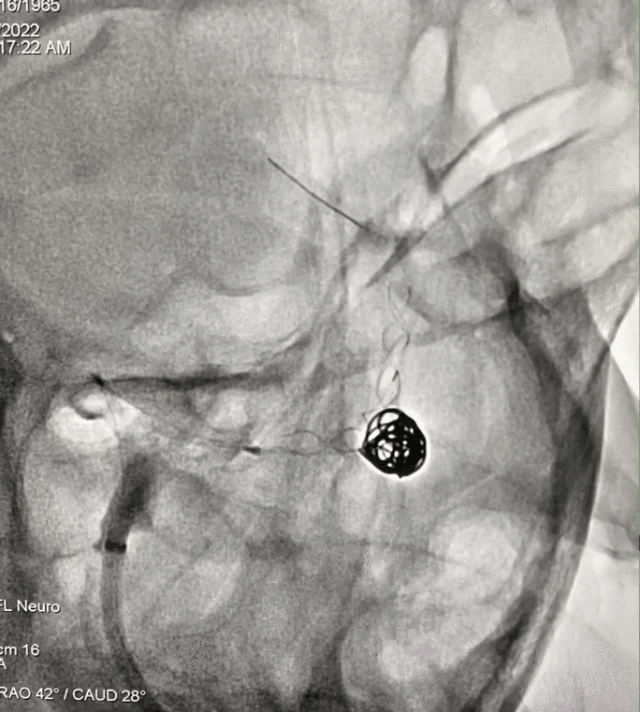

手术过程

畅医达(Choydar)FD输送到位,调整合适位置后逐渐释放‍。

工作位角度

术后正侧位造影片提示颅内血管显影良好,支架打开充分,瘤颈处推密,贴壁良好,动脉瘤内造影剂滞留明显。